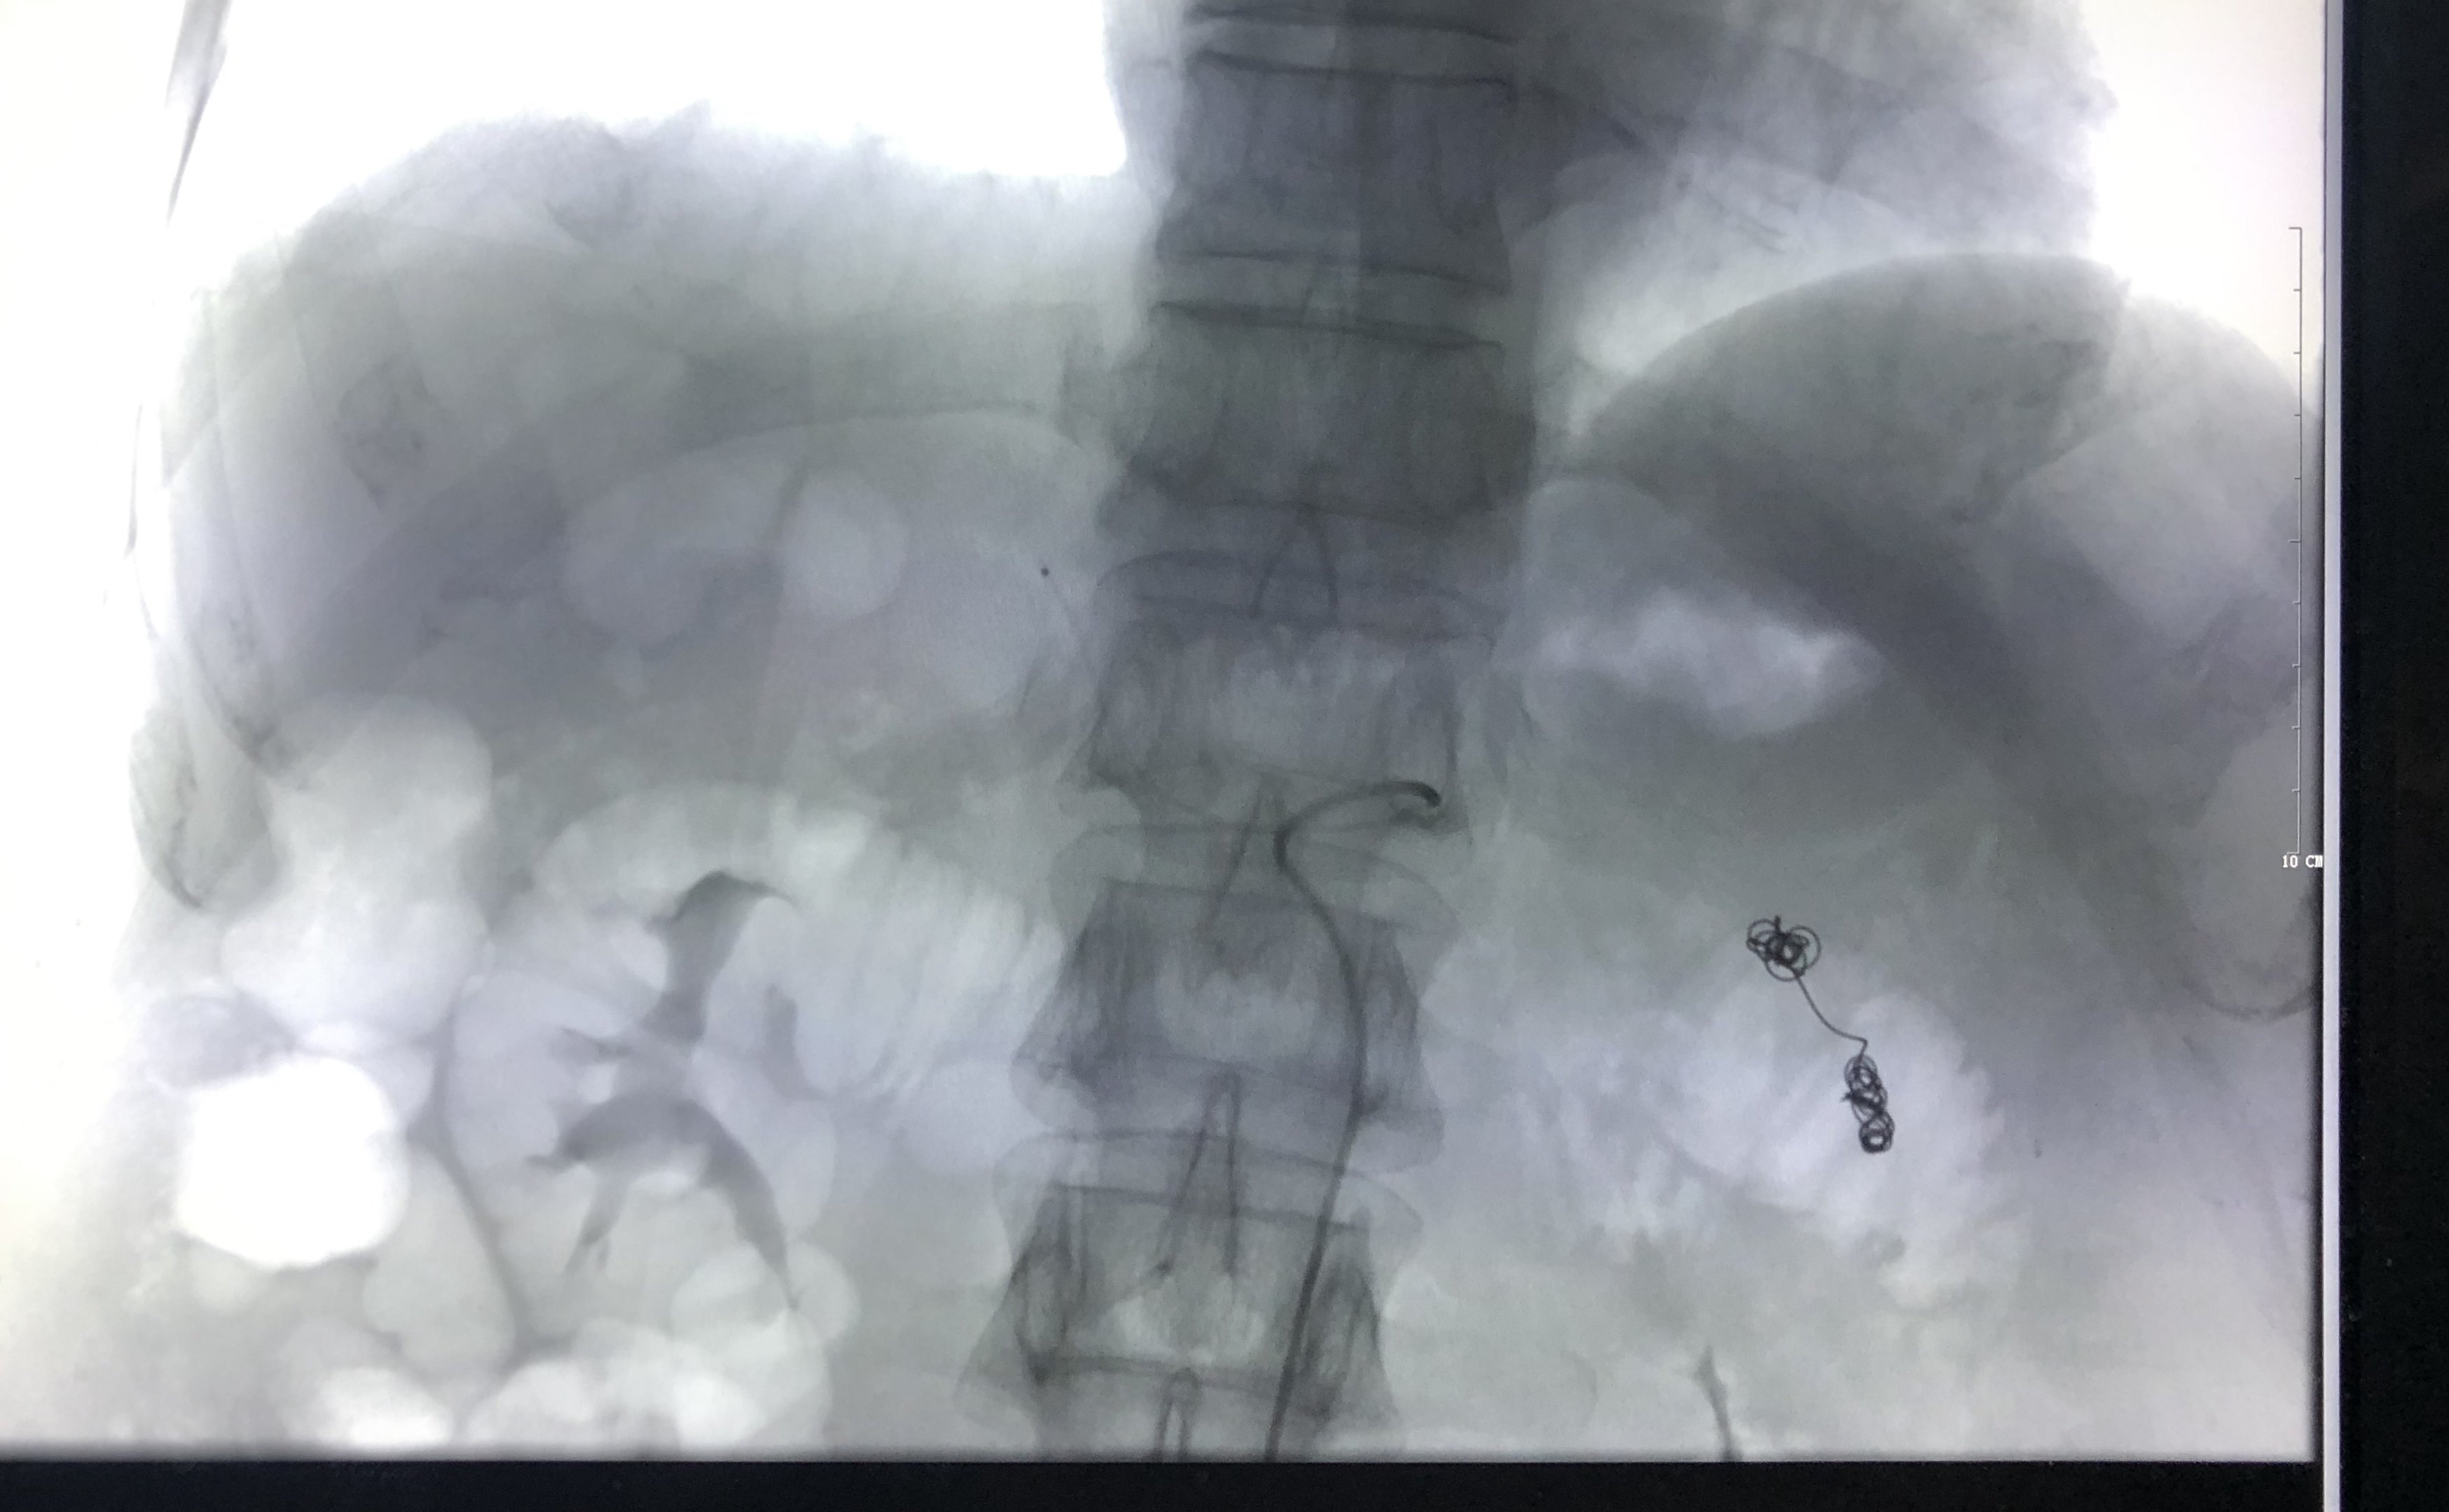

行脾动脉主干栓塞部分阻断脾动脉血流。